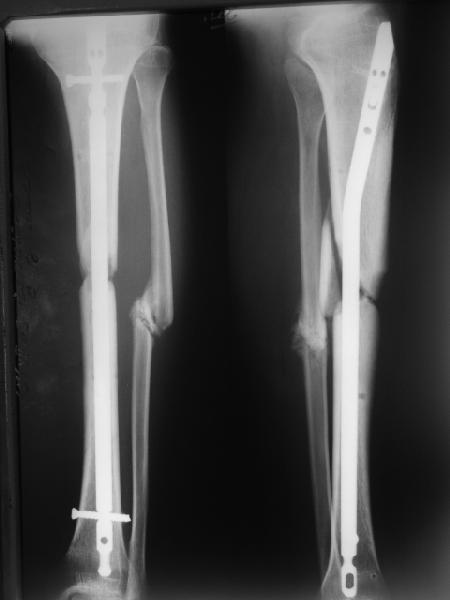

Вполне достаточно закрытого интрамедуллярного остеосинтеза без открытых вмешательств в зоне стыка. Конечно, с рассверливанием. Если есть опасения насчет инфекции, то на гвоздь нанести цемент с ванкомицином.

Гвоздь тут будет эндопротезом диафиза на достаточное время для образования сращения в зоне имеющегося небольшого контакта. И далее страховкой от рефрактур.

Вот пример, тоже открытый перелом, первичный дефект, пробыл в аппарате 5 мес. Титановый гвоздь, сразу динамический, без покрытия. Больше не делали ничего.